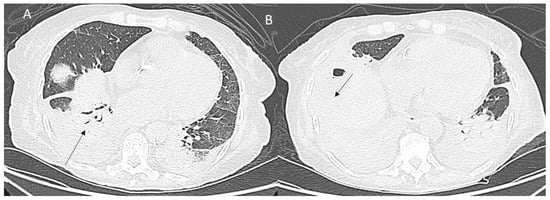

6. Thoracic Complications